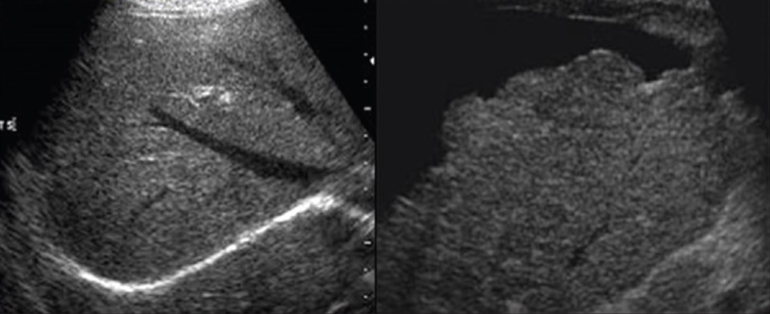

2D US presentation: thin echogenic linear membrane fluttering in lumen creating a true and false lumen

color doppler: fill in both channels → pw shows regular flow in true and weak/no flow in false; asymmetrical kidney perfusion

2D US presentation: focally dilated AO (3 cm or greater), mural hypoechoic thrombus, wall calcifications, usually located infrarenal, can be fusiform or saccular

color doppler: turbulent helical flow